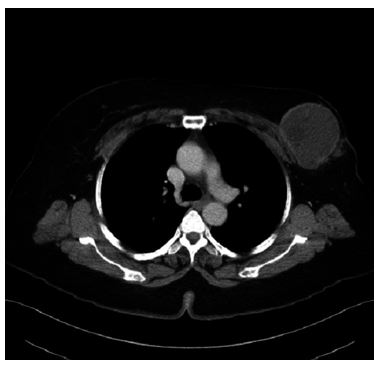

Alamer et al. [13] reported a 66-year-old lady who was known to have hypertension and diabetes mellitus who had presented with a palpable mass within her left breast that was associated with pain over a period of a long time. She did not have any nipple discharge or fever. She also did not have any history of breast trauma, hormone replacement therapy, or a family history of carcinoma of the breast. Her clinical examination showed a large palpable mass which was identified within her left breast with regular borders. Her nipple, areolar, and skin were normal. There was no evidence of palpable lymph node enlargement in her left axilla. Her general examination, systemic examinations and examination of her right breast and right axilla were normal. The results of her investigations including haematology blood tests, biochemistry blood tests, and chest x-ray were normal except elevated serum glucose result. She had a mammogram which showed a large oval and dense mass in the upper outer quadrant of her left breast (see figures 11 and 12). The mass was noted to be lobulated and well-circumscribed in its contours and to have measured 9.2 cm x 7.5 cm. No microcalcification was noted. The nipple, areolar, and skin were normal. The axillary lymph nodes were normal and the right breast was normal. Based upon the mammography examination features of the lump an impression of an usual large dense mass within her left breast was made and coded as BIRAD4A, taking into consideration the age of the patient, and further assessment with ultrasound scan was recommended. The differential diagnoses that were considered included: Phyllodes tumour, pseudo-angiomatous stromal hyperplasia (PASH), and well circumscribed carcinoma of the breast.

She had ultrasound scan of the breast which showed a large heterogeneous and lobulated mass within the upper quadrant of her left breast which had corresponded to the mammographic features. Few internal anechoic cysts were visualized within the peripheral aspects of the breast lesion. Doppler interrogated images did not show any internal vascularity within the mass (see figures 13, 14, and 15). There were no enlarged associated axillary lymph nodes found. She had ultrasound scan-guided biopsy from the lesion. She did have computed tomography (CT) scan for further assessment of the breast lump which did reveal a large hypo-dense mass within her left breast. It also revealed very tiny and thin internal septations were visualized. There was no peripheral enhancement and no internal enhancement. The mass did measure 6.8 cm x 6.2 cm x 9 cm in maximum dimensions (see figures 16 and 17). No axillary lymph nodes were found. The rest of the intra-thoracic and abdominal structures were found to be normal. Pathology examination of the biopsy specimen showed scanty material which had consisted of fragmented eosinophilic membranes that had laminated appearance in keeping with the diagnosis of hydatid cyst. A final diagnosis of hydatid cyst of the breast was made. The patient was referred to the surgeons for surgical excision of the hydatid cyst of the breast at the time of the report of the article. The lesson that needs to be learnt from this case report is the fact that diagnosis of hydatid cyst can be established pre-operatively with careful history taking, clinical examination radiology imaging including ultrasound scan, CT scan, and ultrasound scan-guided biopsy for histopathology/cytology examination which would guide the surgeon to undertake a careful complete surgical excision of the without spillage of the contents of the hydatid cyst.